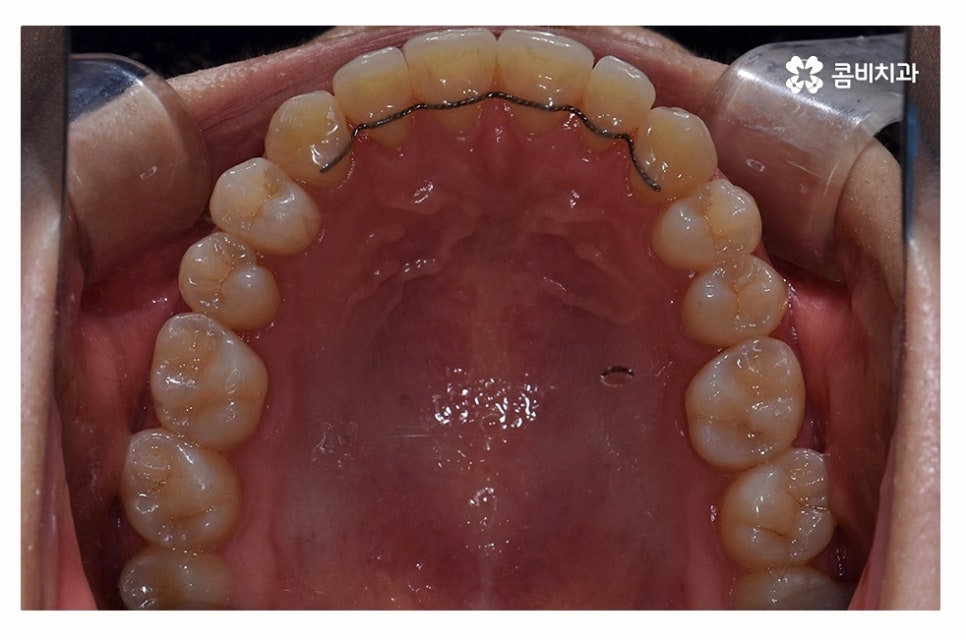

오늘 보여드릴 사례도 덧니교정이 비발치로 진행이 된 사례이며

치아의 이동 공간과 치아 상태, 골격, 얼굴형 등을

종합적으로 판단할 때 비발치로도 진행이 가능했던 사례라고 할 수 있어요.

교정 장치의 선택에 있어서는 다양한 교정 장치의 선택이 가능한데

심미성이 강조된 설측교정부터 콤비교정,

위 환자분의 사례처럼 클리피씨교정이 보편적으로 많이 활용되고 있는데요.

클리피씨교정은 치아의 이동이 일반 장치에 비해 상대적으로

빠르기 때문에 치료 기간이 단축될 수 있으며

통증의 감소, 내원 횟수를 줄일 수 있다는 장점 등이 있어요.